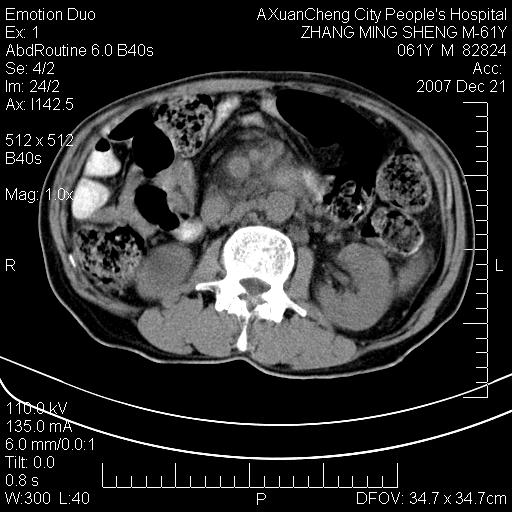

标题: CT11031:M61Y,胰腺占位 [打印本页]

标题: CT11031:M61Y,胰腺占位

大家侃侃门静脉和胆管系统怎么回事,肝内转移?

1,肝硬化,脾大.

2,肝内多发结节状低密度占位,伴门脉及肠系膜上v栓子形成.考虑a;门脉及肠系膜上v血栓后肝改变.b;弥漫型肝癌伴门脉及肠系膜癌栓.

肝硬化,门脉高压,脾肿大;弥漫性肝癌,肝内、门脉、腹膜后淋巴结转移,肝内外胆管扩张,胰头区占位,建议mr检查

胰腺癌伴肝内转移;门脉、肠系膜上v癌栓形成。

考虑为:胰腺癌伴肝脏转移、腹膜后淋巴结转移,门静脉及肠系膜上静脉瘤栓形成。

胰体尾癌伴肝内转移,门静脉及肠系膜上静脉瘤栓形成.

肝硬化,脾大. 胰腺癌伴肝内转移;门脉、肠系膜上v癌栓形成。